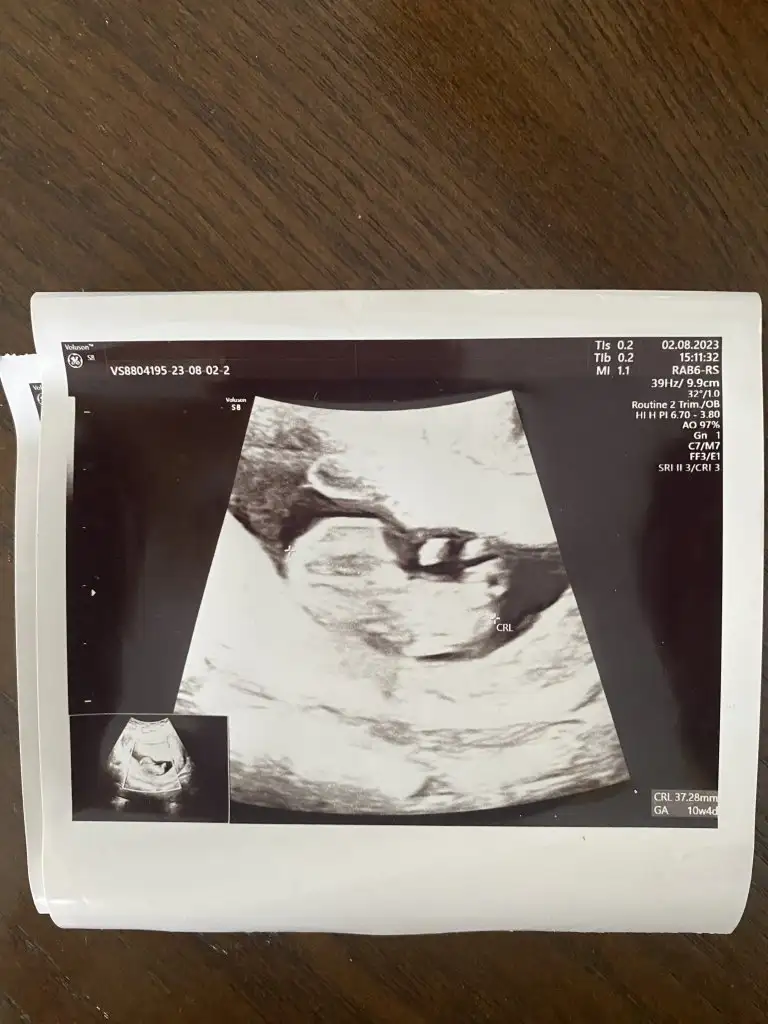

Bana da yorum yapar mısınız rica etsem 🙈 5+4 vajinal ultrason

İlk iki resim ilk ultrason sonrakiler de en son ultrason bende tahmin alabilirmiyim